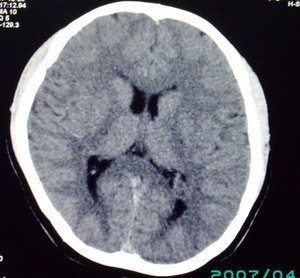

以下是引用九目段在2007-12-24 14:55:00的发言:[br]1,年轻女性[br]2,ct表现:左侧脑室三角区可见一不规则小明显强化的结节,中央见小低密度,侧脑室无扩张。[br]分析:[br]常见的有三种肿瘤好发三角区:[br]1,脉络丛乳头状瘤,好发于年轻者,明显强化,实性,分泌脑脊液,常伴有侧脑室扩大,肿瘤较小可以脑室扩大不明显,不能排除,但小结节尚不易形成坏死腔。[br]2,室管膜瘤,好发于儿童及青少年,明显强化,易坏死,大时伴脑室扩张。[br]3,脑膜瘤,明显强化,圆形,界请,无脑积水,一般不坏死。[br]诊断:[br]左侧脑室三角区结节,考虑室管膜瘤可能性大,不排除脉络丛乳头状瘤和脑膜瘤(因病史较长)。[br][br][本贴已被 九目段 于 2007-12-24 15:13:35 修改过]